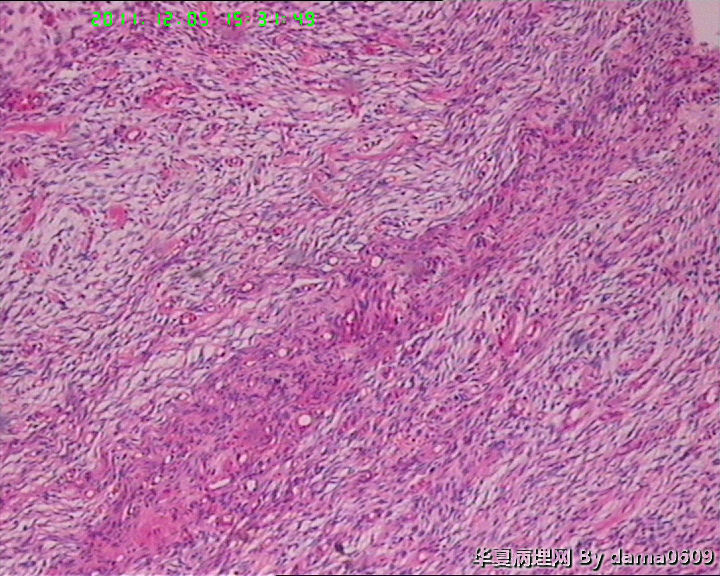

肿物一:镜下见乳腺小叶结构紊乱,小叶内、小叶间间质增生,构成肿瘤主质。增生间质呈梭形细胞样,细胞稀疏、异性不明显,其间见大量胶原纤维,小血管增生,局灶有红细胞渗出。见到一处导管大汗腺化生。

肿物二:镜下呈结节状,结节以导管或小叶为中心,围以增生的间质成分,梭形细胞构成,稀疏,增生的血管呈“鹿角状”。大结节内见局灶间质有出血或红细胞外渗,局灶导管内间质增生呈乳头/分叶状,上皮下无密集增生的间质细胞。结节大小不等,以窄带样纤维细胞束彼此分隔,互不融合,纤维细胞束细胞密集,内有增生的小血管。